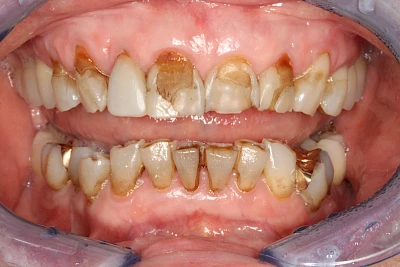

Manche Medikamente wie zum Beispiel das Antibiotikum Tetrazyklin kann bei Einnahme im Zeitfenster der Zahnentwicklung auch irreversibel in die Zahnsubstanz. eingelagert werden. Tetrazyklin verfärbt die jeweils betroffenen Zähne bläulich und sollte deshalb während der Schwangerschaft und bei Kindern nicht verordnet werden.

Daneben gibt es noch seltene genetisch bedingte Schmelz- bzw. Dentinbildungsstörungen (Amelogenesis imperfecta, Dentinogenesis imperfecta), die neben Verfärbungen vor allem auch durch Veränderungen der Oberflächenstrukturen auffallen. In diesen Fällen ist eine engmaschige Betreuung durch den Zahnarzt wichtig.

Dunkle bzw. Rötliche Verfärbung

Ist ein einzelner Zahn deutlich dunkler als die Nachbarzähne kann das ein Zeichen sein, dass der Nerv abgestorben ist. Unter Umständen wurde bereits eine Wurzelkanalbehandlung vom Zahnarzt durchgeführt. Eine Abklärung durch den Zahnarzt ist in jedem Fall sinnvoll.